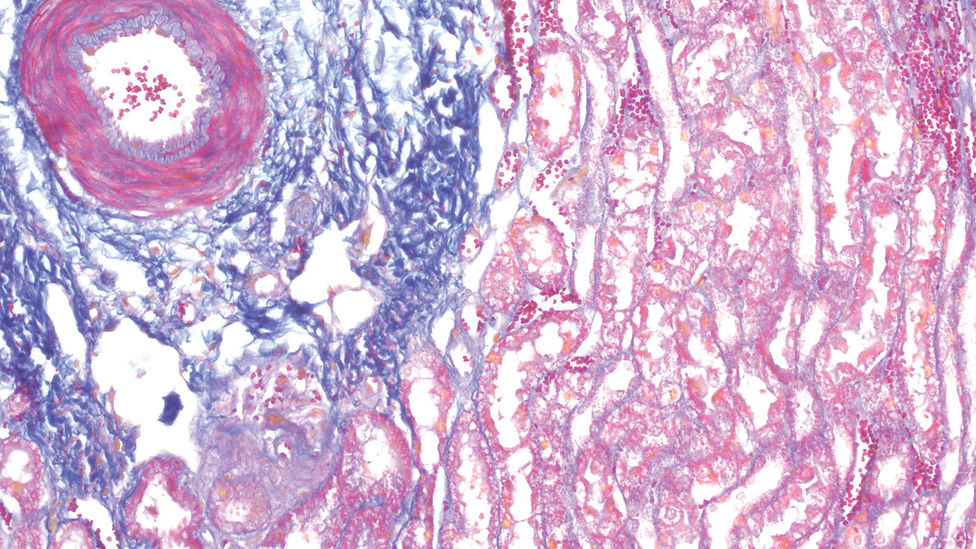

A Mallory trichrome kit három különböző festék és egy kontraszt jelölés segítségével festi meg a szövetekből készült mikroszkópos preparátumokat, azok két alap összetevőjét (izom és kollagén) a fókuszba helyezve. A mintát fukszin savas festékkel kezelve a sejtmagok és izomrostok vöröses-pink árnyalatban jelölődnek. A foszfomolibdénsav molekulák ezután kiszorítják a fukszinsav festéket a kollagénből, így lehetővé téve az anilinkék bekötődését, melynek eredményeként a kollagén a vörössel kontrasztot adó kékre festődik. Az Orange G (mely a legalacsonyabb molekulatömegű komponens) a vörösvértesteket jelöli.